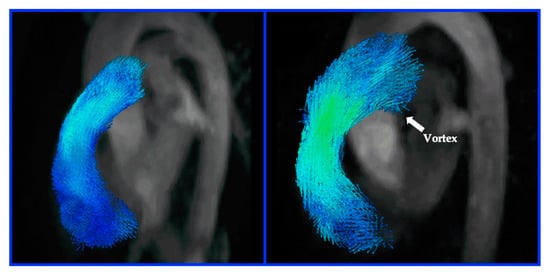

4. Blood Flow Imaging (BFI)